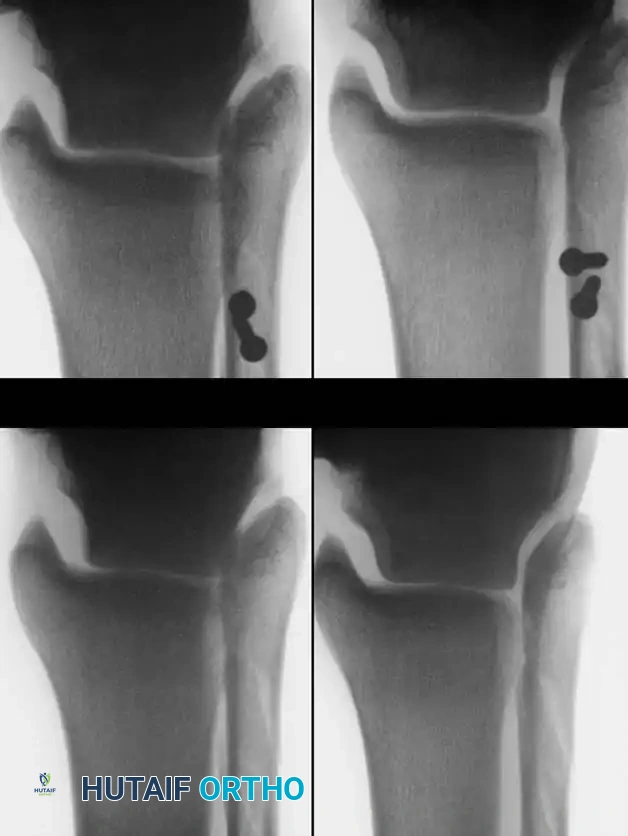

Inversion/eversion stress testing and anteroposterior stress testing (anterior drawer sign) are critical for evaluating acute and chronic instability. However, stress radiographs must demonstrate a statistically significant difference between the injured and contralateral normal ankle to be considered diagnostic.

Anteroposterior Stress Test (Anterior Drawer Sign)

Broström, Castaing, and Delplace heavily emphasized the anterior drawer sign as the primary indicator of an ATFL tear.

Clinically, the maneuver is performed by placing the tip of the thumb on the anterior aspect of the lateral malleolus while palpating the lateral talar process with the base of the thumb. With gentle anterior stress applied to the heel while stabilizing the tibia, the surgeon assesses the degree of anterior translation of the talus relative to the tibial plafond.

Tohyama et al., in a rigorous cadaveric study, demonstrated that applying 30 N of force during the anteroposterior stress test produced a more reliable injured-to-normal displacement ratio than applying 60 N of force. They recommended utilizing a relatively low-magnitude load when evaluating ATFL integrity to prevent secondary restraints from masking the laxity.

Anderson and LeCocq stated that 3 mm of forward talar displacement on stress radiographs is pathological and indicates lateral ligamentous rupture. However, the clinical sensation of the talus subluxating out of the mortise (the "suction sign") is often more diagnostically valuable than absolute millimeter measurements.

Inversion and Eversion Stress Tests (Talar Tilt)

If the lateral ligaments are completely disrupted, the talus tilts abnormally within the mortise under inversion stress. This stress is best applied with the ankle in slight plantarflexion to isolate the ATFL.

- Bonnin's Criteria: A talar tilt of 15 degrees indicates isolated ATFL rupture; 15 to 30 degrees indicates combined ATFL and CFL rupture; >30 degrees indicates rupture of all three lateral ligaments.

- Black's Criteria: Found no absolute clear-cut endpoint but noted that a talar tilt of less than 10 degrees is generally consistent with an isolated ATFL injury.

Hollis et al. noted that if an anteroposterior drawer test shows less laxity in dorsiflexion than in neutral, an isolated ATFL tear is likely. Conversely, laxity present in both 15 degrees of dorsiflexion and neutral indicates combined ATFL and CFL disruption.